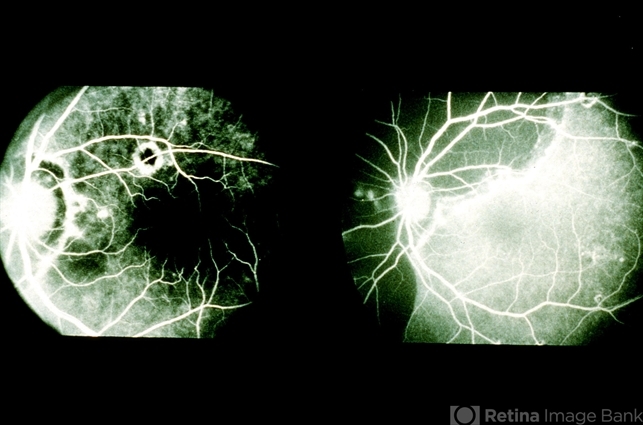

- Subretinal Hemorrhage

- left eye, 20/25, shadow, retinal pigment epithelium, subretinal hemorrhage

- The left eye of 59 year-old black women remained stable with 20/25 vision until she presented a 9-day history of a shadow in the left eye. She had a large sub- RPE and subretinal hemorrhage nasal to the disc. Fluorescein angiography did not identify a site of chooroidal neovascularization. No treatment was done.